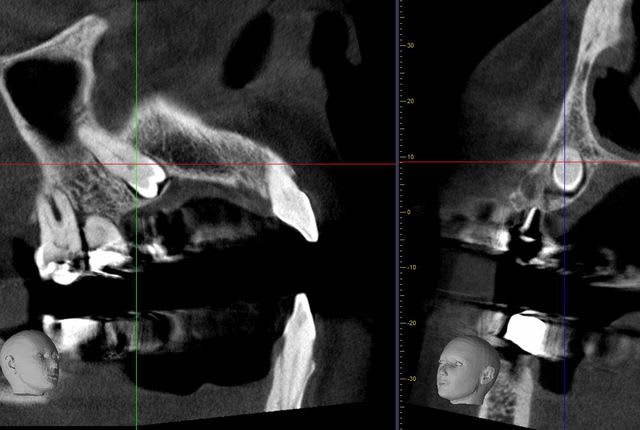

voici un cas avec extraction de 2iéme prémolaire incluse par voie palatine (25) et extraction - implantation - mise en charge immédiate sur 24.

voici 2,3 coupes ...